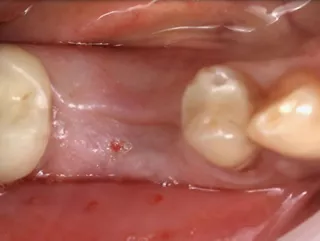

• Situación intraoral del cuadrante inferior derecho.